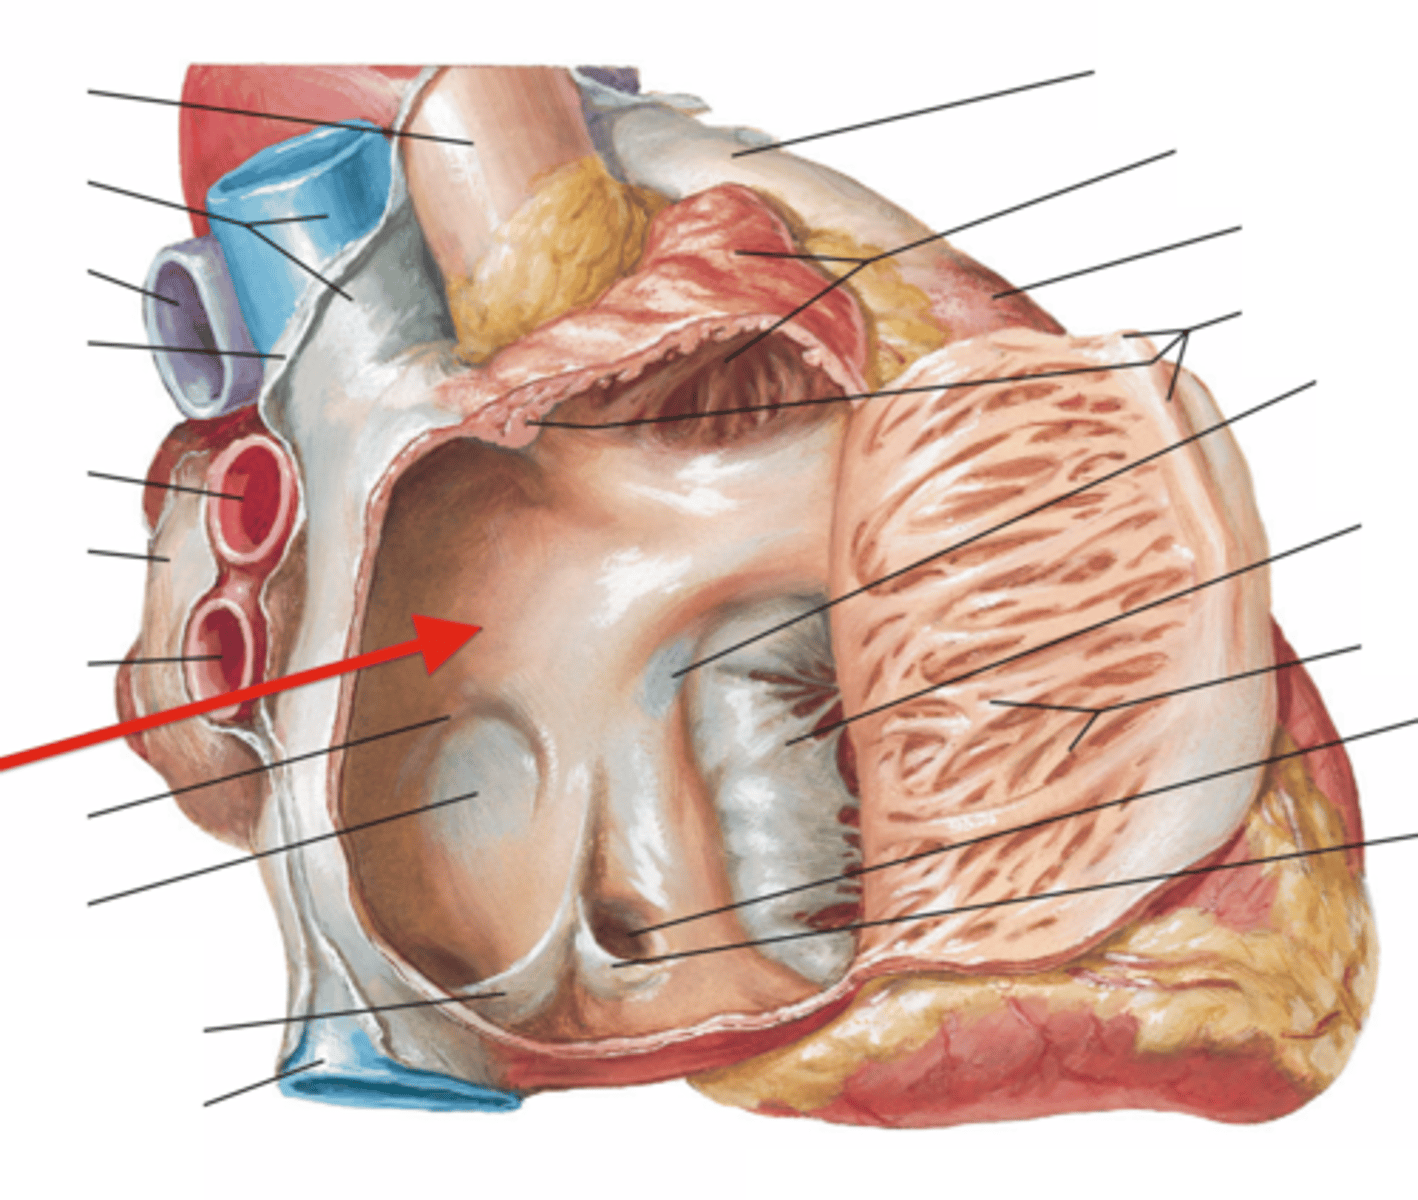

interatrial septum

separates the right and left atria

fossa ovalis

Name this structure located in the right atrium.

oval depression

right auricle

Identify the flap.

dog ear looking

pectinate muscle

muscle that lines the walls of the atrium

striated muscle

sinus venarum

Smooth part of right atrium

below pectinate muscle

opening of the superior vena cava

anterior side opening, above the aorta (space)

opening of the inferior vena cava

posterior side coming down from the heart (space)

opening of the coronary sinus

returns venous coronary circulation to right atrium

Right atrioventricular orifice

opening from right atrium to right ventricle

tricuspid valve

3 cusps. closes as pressure rises in the ventricle to prevent backflow of blood

papillary muscles (3)

they tug at your heart strings

carrot

tendinous cords

heart strings

trabeculae carneae

ridges of cardiac muscle

conus arteriosus

cone-shaped part of the ventricles that leads into the pulmonary trunk (narrowing)